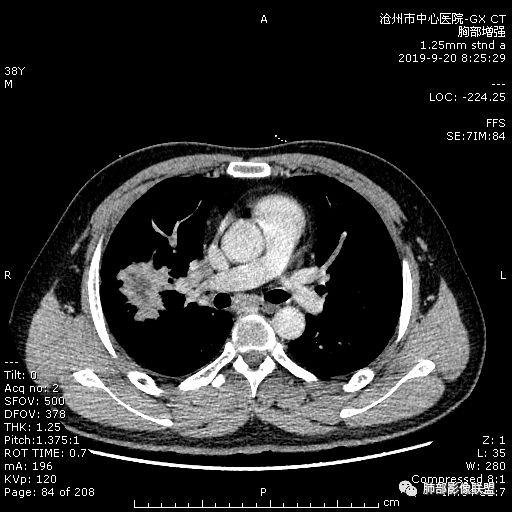

青年男性,肿瘤指标无异,右上中肺团片影,形态不规,跨叶生长,

病灶内见坏死,增强边缘强化,考虑炎性肉芽肿,TB,鉴别鳞。

年轻男性,咳嗽2月,痰中带血,胸痛,炎症指标稍高,肿标正常。影像,右肺上叶不规则团块影,浅分叶,伴边界不清磨玻璃影,从外周向内分布,局部胸膜增厚,病灶中央坏死,坏死边界尚清,空洞形成,空洞内壁光滑;考虑炎性肉芽肿性病变,结核可能,鉴别恶性肿瘤及真菌感染。病灶分布特点不考虑隐球。

右肺上叶不规则病灶,密度不均,有分叶,边缘不清,中央有坏死,坏死壁尚光滑,增强壁有强化,病灶有外朝内,整体收缩为主,慢性病程,考虑炎性病变,肺脓肿或者结核,淋巴结肿大,支气管截断,胸膜脂肪间隙变窄,加个鉴别恶性肿瘤。

近端支气管截断,非坏死区的强化特征,肺门区肿大淋巴结,所谓的“月牙铲”,这些强烈提示病变是癌;胸膜、相邻肋间肌的改变,提示是炎性改变;在癌与炎性肉芽肿之间,哪个占主导地位?是解决问题的关键;坏死区的形态,也支持炎性病变。

右肺上叶分叶状肿块(冠状位尤为明显),内见液化坏死,支气管截断,收缩力强,周围有片状影,右侧腋窝及纵隔淋巴结增大,增强有强化,定性恶性病变,脓肿形态及临床症状不符,暂排除。

右上肺占位,总体膨胀性生长,支气管截断,坏死明显,常规考虑鳞。

38岁,男性,慢性咳嗽2月,右胸痛8天,无发热;白细胞高,肿瘤标志物不高;右上肺不规则块状影,周围有磨玻璃影,边界清,整体有膨胀感,分叶,与胸膜糊墙,并见栽赃,增强肿块中央坏死,周边强化。综合考虑,考虑恶性,鳞癌可能。

38岁,男性,慢性咳嗽2月,右胸痛8天,无发热。白细胞高,肿瘤标志物不高。右上肺不规则块状影,周围有磨玻璃影,边界模糊,整体有膨胀感,分叶,与胸膜糊墙,可疑栽赃,增强肿块中央坏死,边界清,周边强化明显,强化区有低密度影,壁不规则,跨叶生长,支气管截断,伴支气管扩张,综合考虑腺癌

中年男性,咳嗽2月,伴胸痛8天,少许痰血,无发热中性粒明显增高,低氧,肿标不高,右肺上叶不规则实性肿块,深分叶,局部凹陷呈月牙铲改变,多坏死,多空泡,前段支气管分支似见堵塞,2R、4R、10R和7区淋巴结肿大。考虑肺癌可能,建议支气管镜活检

晨读病例,右肺上叶胸壁处占位,边缘分叶毛刺,收缩力强,多发坏死,远端支气管截断,不均匀性强化,血管穿行变窄,纵隔多发淋巴结肿大,考虑恶性肿瘤,首先考虑腺癌

膨隆、深分叶,支气管截断,叶裂推移,淋巴结肿大,均提示恶性可能;但毕竟年轻,血象高,内部坏死边界清晰,局部收缩感,提示感染可能,另外内部数个小空洞改变,是扩张支气管吗?需要连续层面看,如果是,就更支持感染。

右肺上叶不规则实性肿块,有膨胀有收缩,多坏死,空泡,右肺门淋巴结肿大,考虑肺癌,就是才38岁,太年轻了

晨读:青年男性,咳嗽痰中带血,亚急性起病,白细胞高,超敏高,CT示右肺上叶分叶肿块,内部坏死,病灶周围小结节,近端支气管通过,纵隔淋巴结肿大,综合考虑肉芽肿型结核较鳞癌可能大

晨读:右肺上叶不规则团块,深分叶,膨胀为主,有部分收缩,叶间裂牵拉上移,内多液化坏死,有支气管扩张,右肺上叶大支气管近端通畅,远端堵塞,说明肿块来源于外周,纵隔及右肺门淋巴结肿大,胸膜糊墙为主,年轻人,肿标不高,炎性指标高,综合考虑炎性肉芽肿放前面脓肿,结核,肿瘤放后面。

良孑: 晨读病例,右上肺不规则实变,边界模糊,内可见多发坏死灶,腔内坏死壁厚薄不均,有支气管截断,强化时病灶内血管受累,右肺门淋巴结肿大,从影像上看恶性鳞癌征象较多,但病变明显强化,且坏死壁是均匀强化,炎性标志物高,患者年龄较轻,病史较长,病灶内多个坏死液化灶且内缘光整,综和判断,首先考虑亚急性肺脓肿,其次考虑鳞癌

病灶垮叶,强化明显,病灶内见坏死、空泡,周围模糊,考虑放线菌病?鉴别鳞癌

青年男性,右肺上叶肿块,分叶,明显膨隆,内见空洞与支气管相通,增强环形强化,中心液化坏死。实验室鳞癌指标不高。考虑:1,结核,2,肺脓肿。鉴别鳞癌。

中年男性,咳嗽2月病史伴胸疼。白细胞及中性粒细胞高。右上肺团块影,边缘平直内收,与胸膜宽基底相连,胸膜肥厚,肿块内多灶性坏死,有空泡征,支气管进入,走行自然,近端有阻塞,考虑感染性疾病,肺脓肿。但是有深分叶,鳞癌合并感染也不排除。

右肺上叶不规则病灶,密度不均,有分叶,边缘不清,中央有坏死,坏死壁尚光滑,增强壁有强化,考虑肺脓肿或者结核,但是淋巴结肿大,支气管截断,不除外肿瘤。